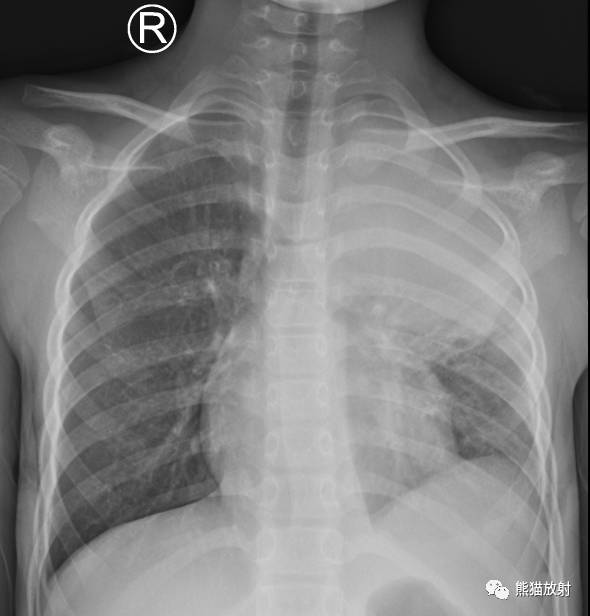

↓ 患儿9岁,咳嗽、高热。左肺炎症并左上肺肺实变、不张(X、CT)